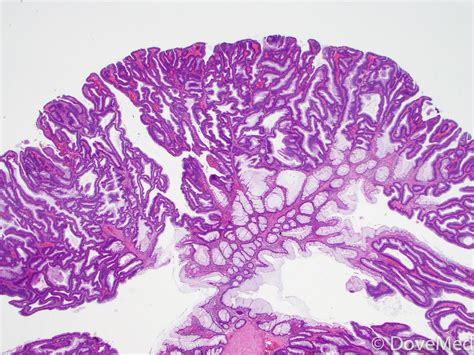

What is a Tubular Adenoma of the Colon?

A tubular adenoma is a type of polyp that forms on the inner lining of the colon. These polyps are composed of glandular tissue and are characterized by their tubular shape. Tubular adenomas are the most common type of adenomatous polyps, which are known to have the potential to become malignant if left untreated. Early detection and removal of these polyps are essential for preventing the development of colorectal cancer.